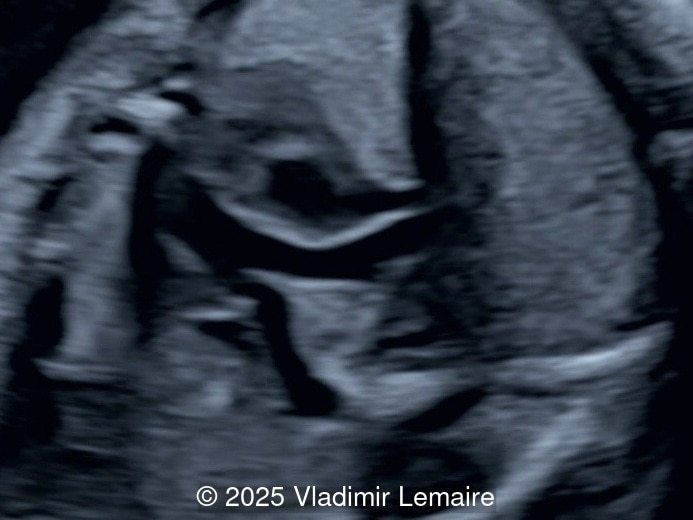

Video 1 Basal four-chamber view. © 2025 Vladimir Lemaire

Basal four-chamber view. Note the presence of an atretic tricuspid valve (yellow arrow) as well as a ventricular septal defect (*).

Image 1 Basal four-chamber view. Note the presence of an atretic tricuspid valve (yellow arrow) as well as a ventricular septal defect (*).

The four-chamber view in tricuspid atresia is diagnostic. It reveals a small right ventricle, a ventricular septal defect, and the absence of a right-sided atrioventricular junction. The size of the right ventricle mainly depends on the size of the ventricular septal defect: the smaller the ventricular septal defect, the smaller the right ventricle. Its contractility is normal with no myocardial thickening. The atretic tricuspid valve appears as echogenic thickened tissue and the right atrium is slightly dilated. The interatrial communication is large and there is often a redundant flap of the septum secundum that bulges into the left atrium. The interatrial and interventricular septa are malaligned.